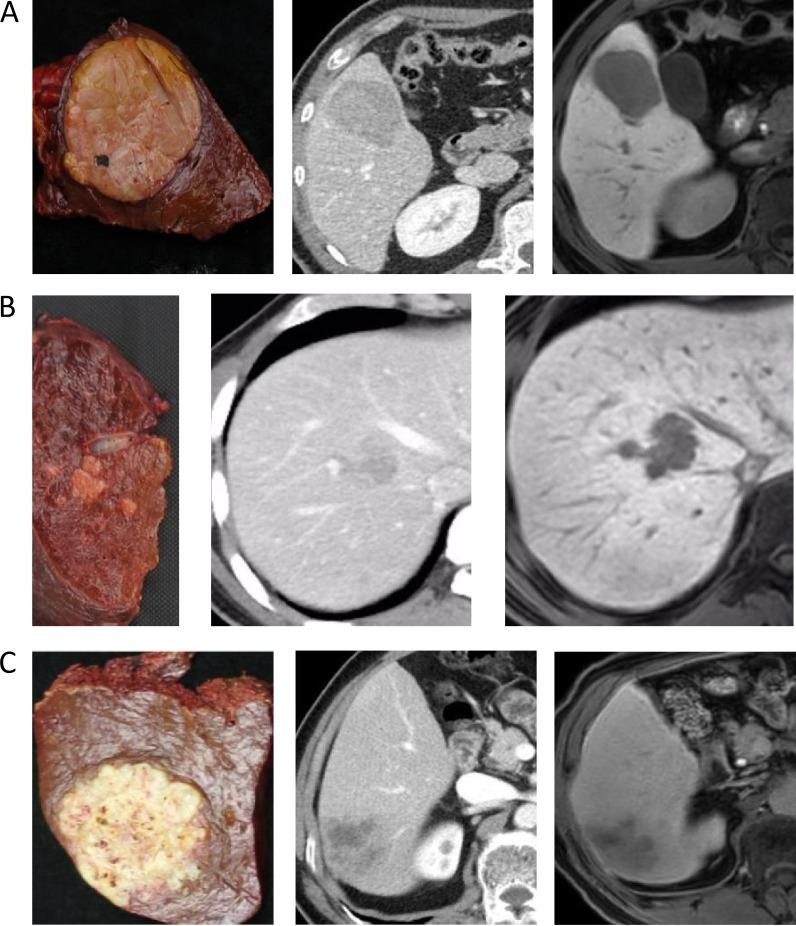

Accurate gross classification through imaging is critical for determination of hepatocellular carcinoma (HCC) patient prognoses and treatment strategies. The present retrospective study evaluated the utility of contrast-enhanced computed tomography (CE-CT) combined with gadolinium-ethoxybenzyl diethylenetriamine pentaacetic acid-enhanced magnetic resonance imaging (EOB-MRI) for diagnosis and classification of HCCs prior to surgery. Ninety-four surgically resected HCC nodules were classified as simple nodular (SN), SN with extranodular growth (SN-EG), confluent multinodular (CMN), or infiltrative (IF) types. SN-EG, CMN and IF samples were grouped as non-SN. The abilities of the two imaging modalities to differentiate non-SN from SN HCCs were assessed using the EOB-MRI hepatobiliary phase and CE-CT arterial, portal, and equilibrium phases. Areas under the ROC curves for non-SN diagnoses were 0.765 (95% confidence interval [CI]: 0.666-0.846) for CE-CT, 0.877 (95% CI: 0.793-0.936) for EOB-MRI, and 0.908 (95% CI: 0.830-0.958) for CE-CT plus EOB-MRI. Sensitivities, specificities, and accuracies with respect to identification of non-SN tumors of all sizes were 71.4%, 81.6%, and 75.5% for CE-CT; 96.4%, 78.9%, and 89.3% for EOB-MRI; and 98.2%, 84.2%, and 92.5% for CE-CT plus EOB-MRI. These results show that CE-CT combined with EOB-MRI offers a more accurate imaging evaluation for HCC gross classification than either modality alone.

通过影像学进行准确的大体分类对于确定肝细胞癌(HCC)患者的预后和治疗策略至关重要。本回顾性研究评估了对比增强计算机断层扫描(CE-CT)联合钆塞酸二钠增强磁共振成像(EOB-MRI)在术前诊断和分类HCC中的应用价值。94个手术切除的HCC结节被分类为单纯结节型(SN)、伴结节外生长的SN(SN-EG)、融合多结节型(CMN)或浸润型(IF)。SN-EG、CMN和IF样本被归为非SN组。使用EOB-MRI肝胆期和CE-CT动脉期、门静脉期及平衡期评估两种成像方式区分非SN与SN HCC的能力。CE-CT诊断非SN的ROC曲线下面积为0.765(95%置信区间[CI]:0.666 - 0.846),EOB-MRI为0.877(95%CI:0.793 - 0.936),CE-CT联合EOB-MRI为0.908(95%CI:0.830 - 0.958)。对于所有大小非SN肿瘤的识别,CE-CT的敏感性、特异性和准确性分别为71.4%、81.6%和75.5%;EOB-MRI分别为96.4%、78.9%和89.3%;CE-CT联合EOB-MRI分别为98.2%、84.2%和92.5%。这些结果表明,与单独使用任何一种方式相比,CE-CT联合EOB-MRI对HCC大体分类提供了更准确的影像学评估。